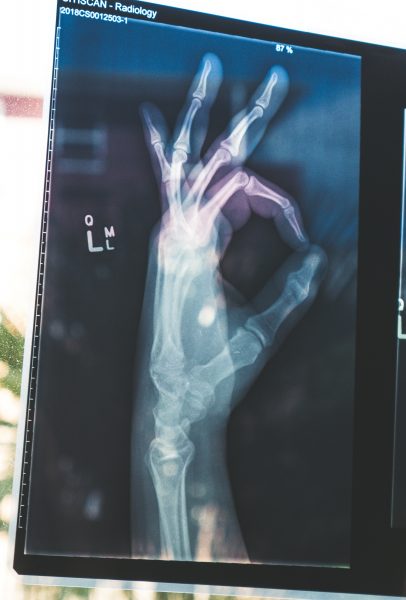

When it comes to movement, having strong bones is essential for keeping yourself upright. Bones provide the structural framework for the entire body and work together with muscles as levers to produce controlled movements.

Repeated footstrike, which happens with long-distance running and continuous backpacking, can lead to tiny cracks in the bone, otherwise known as stress fractures. This occurs when bones are subjected to sudden and unaccustomed increases in force and loads without enough recovery time. Cells can’t resorb faster than your body can replace them.

- Stress Fractures. If you experience a stress fracture, get your blood calcium level measured, and a DXA scan to assess bone mineral density.